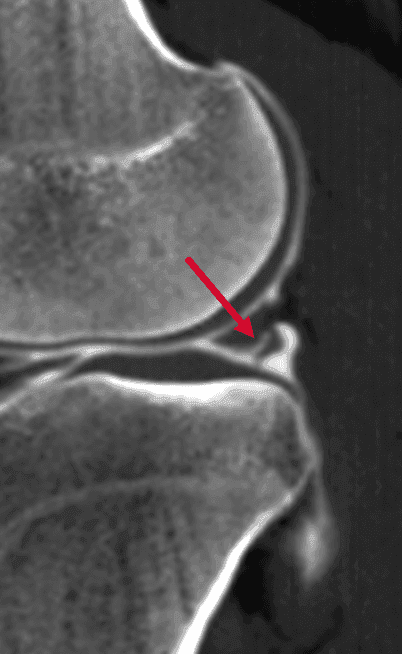

Un arthroscanner complémentaire est réalisé et démontre la présence d'une fissure méniscale longitudinale incomplète (flèche rouge), très proche du mur méniscal postérieur qui présente un aspect soufflé après remplissage de la fissure par le produit de contraste.

Sagittal arthroscanner